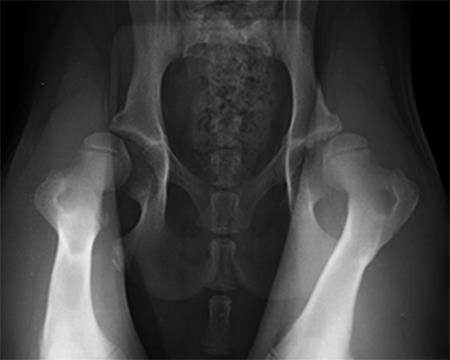

Radiographic examination at 6 months postsurgery revealed stable implants, excellent coxofemoral conformation, and no evidence of osteoarthritis of the right hip. The left acetabulum was mildly shallow and mild subluxation of the femoral head was present at follow-up examination (Fig 6). Early osteophytosis in the region of the left femoral neck was evident. The dog was using the right hind leg normally and was showing no signs of instability or pain of the right hip. Mild instability and pain of the left hip was present on palpation. The dogs left hip was treated with a joint supplement and NSAIDs as needed. Future THR will be performed if clinical signs no longer respond to medical treatment.